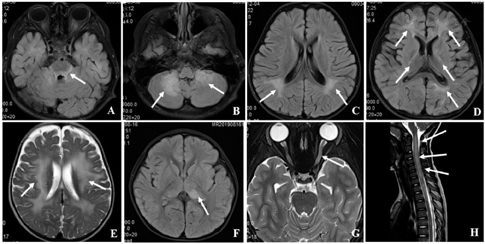

在78次病程事件中,76.9%(60/78)颅脑MRI显示新发病灶。脑部病变范围广泛多样(图1),液体衰减反转恢复(FLARE)常表现为高信号,部分可表现为融合性白质病变,呈蓬松状弥漫分布,边缘欠清;眼眶MRI可表现为双侧或单侧视神经增粗或信号改变,可累及视交叉。常见颅内损伤部位分别为皮质旁白质(66.7%,40/60)、视神经(35.0%,21/60)、基底节区(31.7%,19/60)、小脑(28.3%,17/60)、脑干(18.3%,11/60)和胼胝体(18.3%,11/60)。新发病灶患儿治疗后颅脑MRI病变完全消失10例(16.7%),好转26例(43.3%)。3.3%(2/60)颅脑MRI在初次及复发时表现为脑白质营养不良样模式。9例患儿颅脑增强MRI仅表现为脑膜线样强化,伴脑脊液白细胞计数轻度增高,为非ADEM样脑膜/脑炎表现。患儿脊髓MRI可表现为病灶轻度肿大,少量斑片或条状高信号影(图1)。78次病程事件中脊髓MRI损伤15次(19.2%),包括胸髓(40.0%,6/15)、圆锥脊髓(40.0%,6/15)、颈髓(26.7%,4/15)和腰髓(13.3%,2/15)。

注:图中箭头所指部位病变分别为脑干(A),双侧小脑(B),顶叶白质(C),内囊后肢及脑室旁(D),皮质旁白质(脑白质营养不良样(E),丘脑(F),视神经(G),脊髓(H);MOGAD=抗髓鞘少突胶质细胞糖蛋白免疫球蛋白G抗体相关疾病